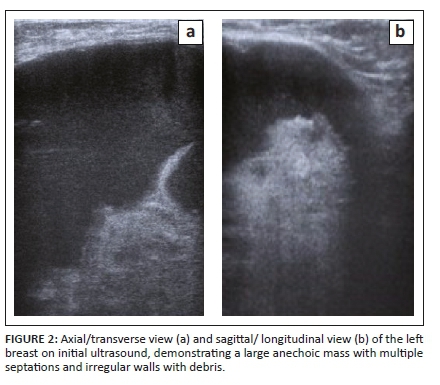

She was then referred to the radiology department for a mammogram and a breast ultrasound. The left mammogram demonstrated a 126 mm × 110 mm, circumscribed, round mass within the upper outer quadrant. The mass was homogenous with mass effect on the adjacent glandular tissue as displayed in Figures 1a and 1b. Ultrasound of the left breast demonstrated a large anechoic mass with septations and an irregular inner thickened wall with debris as displayed in Figures 2a and 2b. The right mammogram and ultrasound were within normal limits. The mass was classified as a Breast Imaging-Reporting and Data Systems (BI-RADS) 4A lesion and the patient was referred back to the surgeons. An image-guided biopsy was not performed at this stage because the patient was awaiting histology results for the biopsy performed by the surgeon.